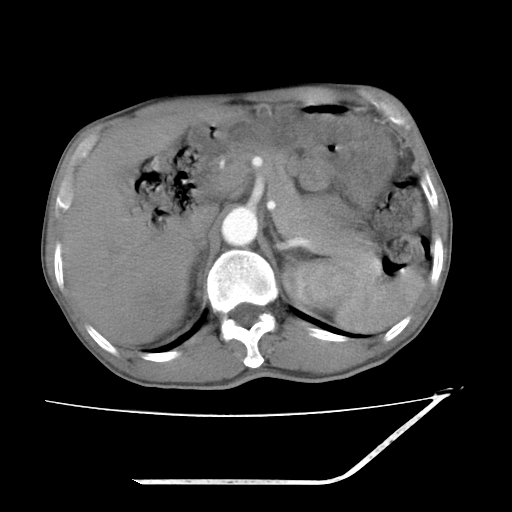

增强

考虑右肾盂癌,肾动脉受侵,右肾功能减退,右肾盂输尿管积水,管壁增厚,考虑种植转移,应该把下面扫完的

支持右侧肾盂癌伴肾静脉瘤栓形成可能性大,右肾结石.肝右叶后段低密度影,不除外转移.

右肾盂旁ca并肾静脉瘤栓形成/肾功能降低。

右肾结石。

右肾盂癌,肾动脉受侵,右肾盂输尿管积水,管壁增厚,考虑种植转移

支持 右侧肾盂癌伴肾静脉瘤栓形成可能性大,右肾结石;肝右叶后段低密度影,不除外转移。

1.右侧肾盂癌伴肾盂积水。

2.肾脏功能减退,原因有:(1)肾动脉受侵。(2)肾静脉受侵(3)肾积水,等。本例,肾动脉显影较好,但受压明显;肾静脉无明显显示,受压或静脉癌栓,下腔静脉腔内未见明显充盈缺损。

3.右侧上段输尿管扩张,原因:(1)积水所致;(2)种植。